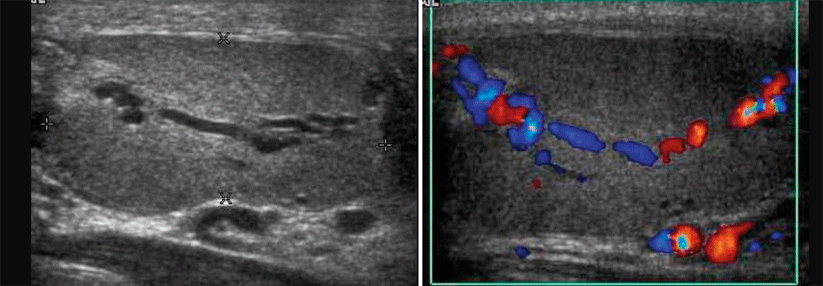

Daran nahmen an sechs Hamburger Gymnasien 548 Schülerinnen und Schüler zwischen 16 und 20 Jahren teil. Das Ergebnis enttäuscht: Nur etwa 60 % beantworteten alle Fragen korrekt. Die Jugendlichen sind sich anscheinend des Problems nicht bewusst, meinen die Autoren. Die zweite Jugenduntersuchung (J2) böte Jungs die Möglichkeit zu einem Besuch beim Urologen. Der Facharzt könnte hinsichtlich Selbst­untersuchung anleiten und aufklären, wenn der Patient bislang unbekannte Strukturen wie Nebenhoden oder Samenstrang ertastet hat.